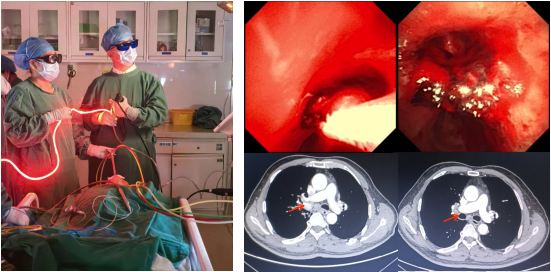

气道肿瘤光动力治疗

硬质镜下气道肿物开通术